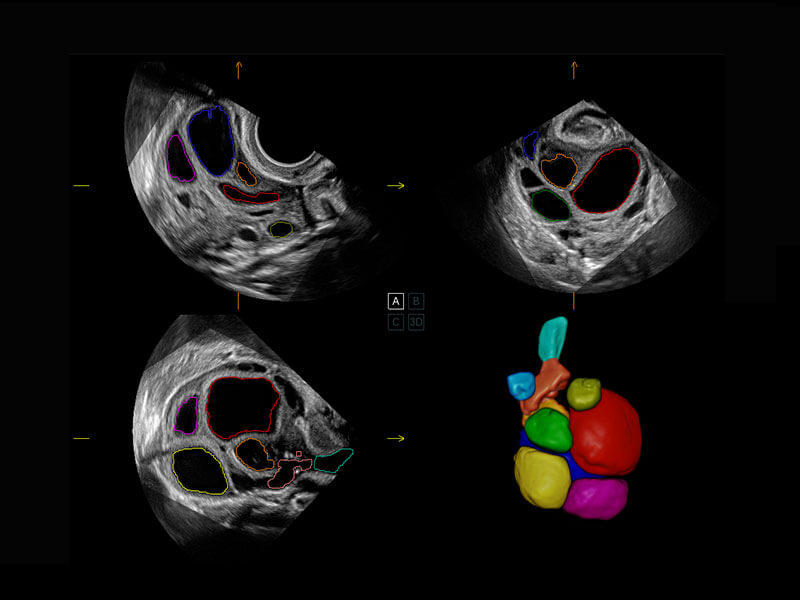

P60搭載一系列胎兒心臟成像技術(shù),實現(xiàn)精細的胎兒心臟評估。

四腔切面

四腔心血流

右室雙出口

胎心容積成像